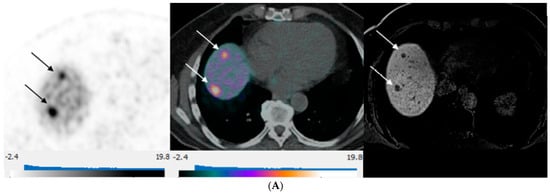

3. Results